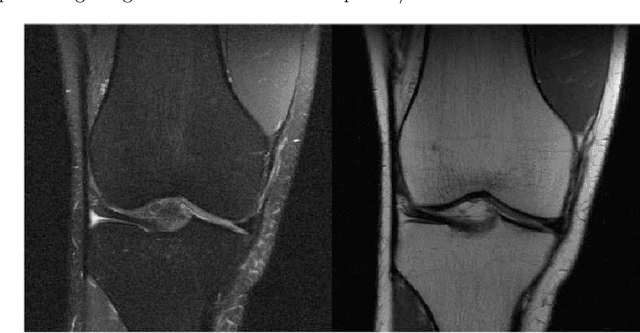

Abstract:Magnetic Resonance Imaging (MRI) scans are time consuming and precarious, since the patients remain still in a confined space for extended periods of time. To reduce scanning time, some experts have experimented with undersampled k spaces, trying to use deep learning to predict the fully sampled result. These studies report that as many as 20 to 30 minutes could be saved off a scan that takes an hour or more. However, none of these studies have explored the possibility of using masked image modeling (MIM) to predict the missing parts of MRI k spaces. This study makes use of 11161 reconstructed MRI and k spaces of knee MRI images from Facebook's fastmri dataset. This tests a modified version of an existing model using baseline shifted window (Swin) and vision transformer architectures that makes use of MIM on undersampled k spaces to predict the full k space and consequently the full MRI image. Modifications were made using pytorch and numpy libraries, and were published to a github repository. After the model reconstructed the k space images, the basic Fourier transform was applied to determine the actual MRI image. Once the model reached a steady state, experimentation with hyperparameters helped to achieve pinpoint accuracy for the reconstructed images. The model was evaluated through L1 loss, gradient normalization, and structural similarity values. The model produced reconstructed images with L1 loss values averaging to <0.01 and gradient normalization values <0.1 after training finished. The reconstructed k spaces yielded structural similarity values of over 99% for both training and validation with the fully sampled k spaces, while validation loss continually decreased under 0.01. These data strongly support the idea that the algorithm works for MRI reconstruction, as they indicate the model's reconstructed image aligns extremely well with the original, fully sampled k space.